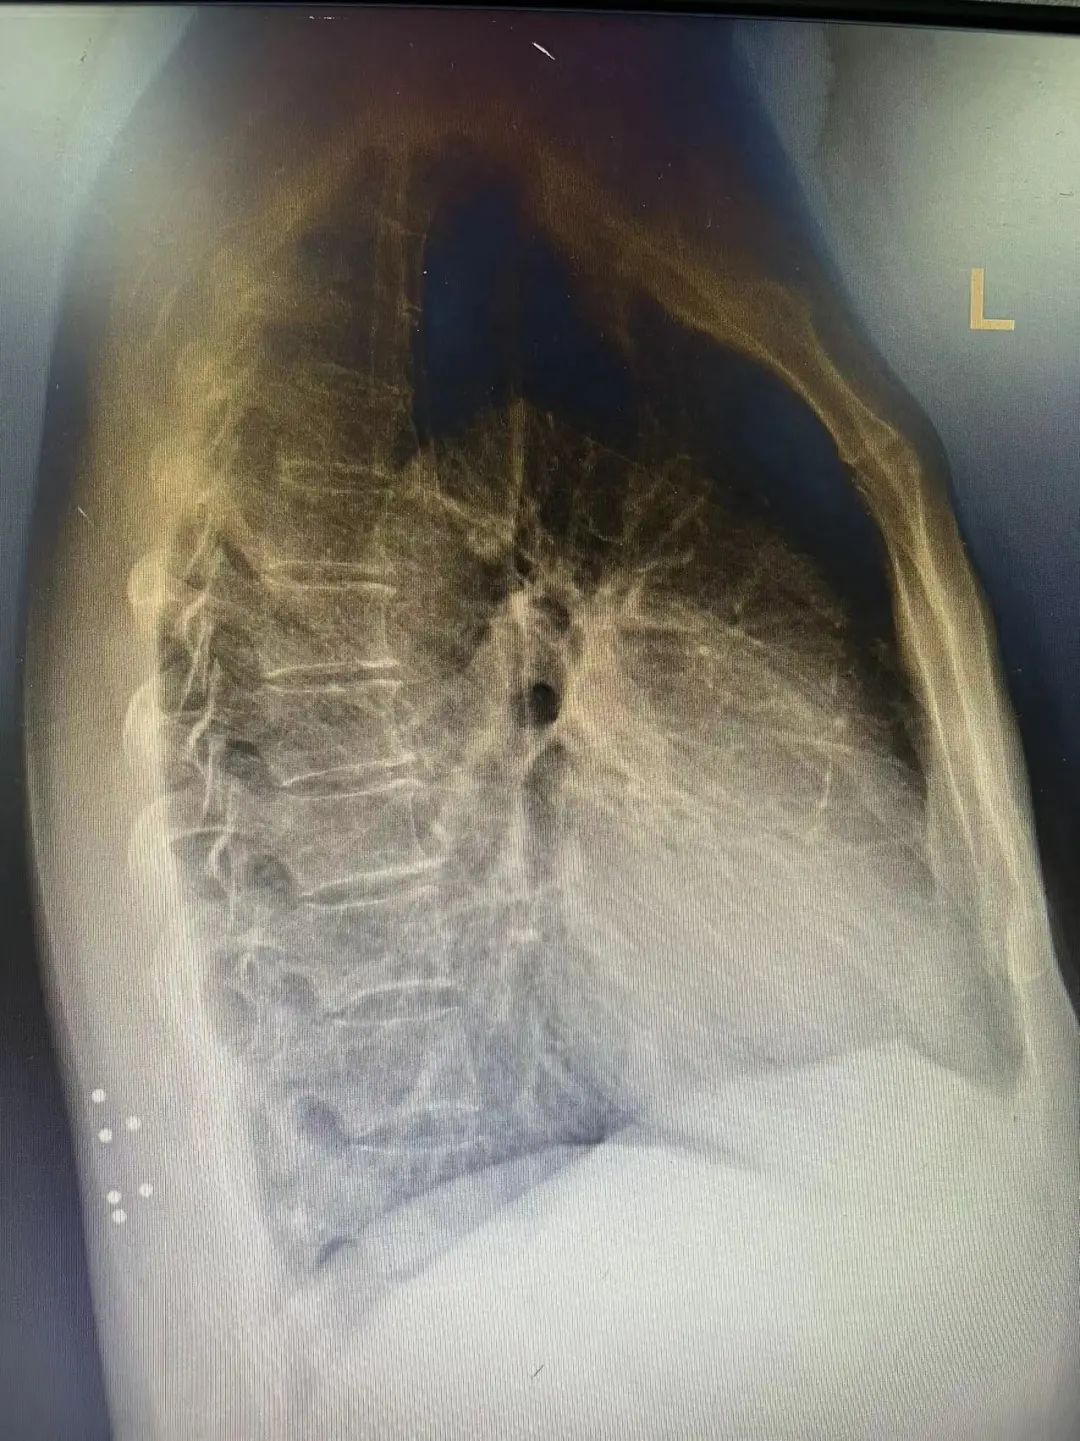

X光片报告显示,邓先生的右侧腰背部存在6粒金属异物,均被周围组织黏连包裹,分离难度大。经过近1个小时的手术,医生从邓先生体内取出了6颗钢珠,对比钢珠大小参差不一,表面粗糙不已,失去了当年的光泽。

X光片报告显示,邓先生的右侧腰背部存在6粒金属异物。